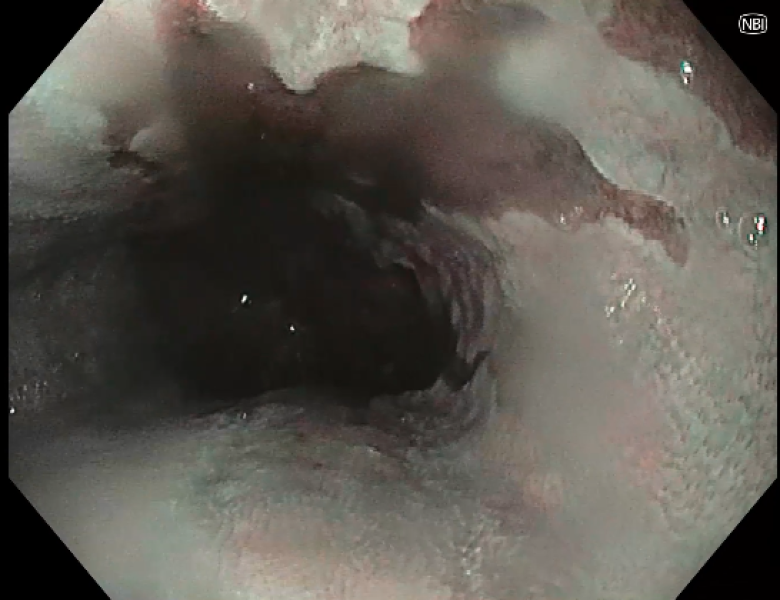

From ring to ring on the road to the eosinophilic abyss - a doubly complicated presentation of Eosinophilic oesophagitis!

Fotografia